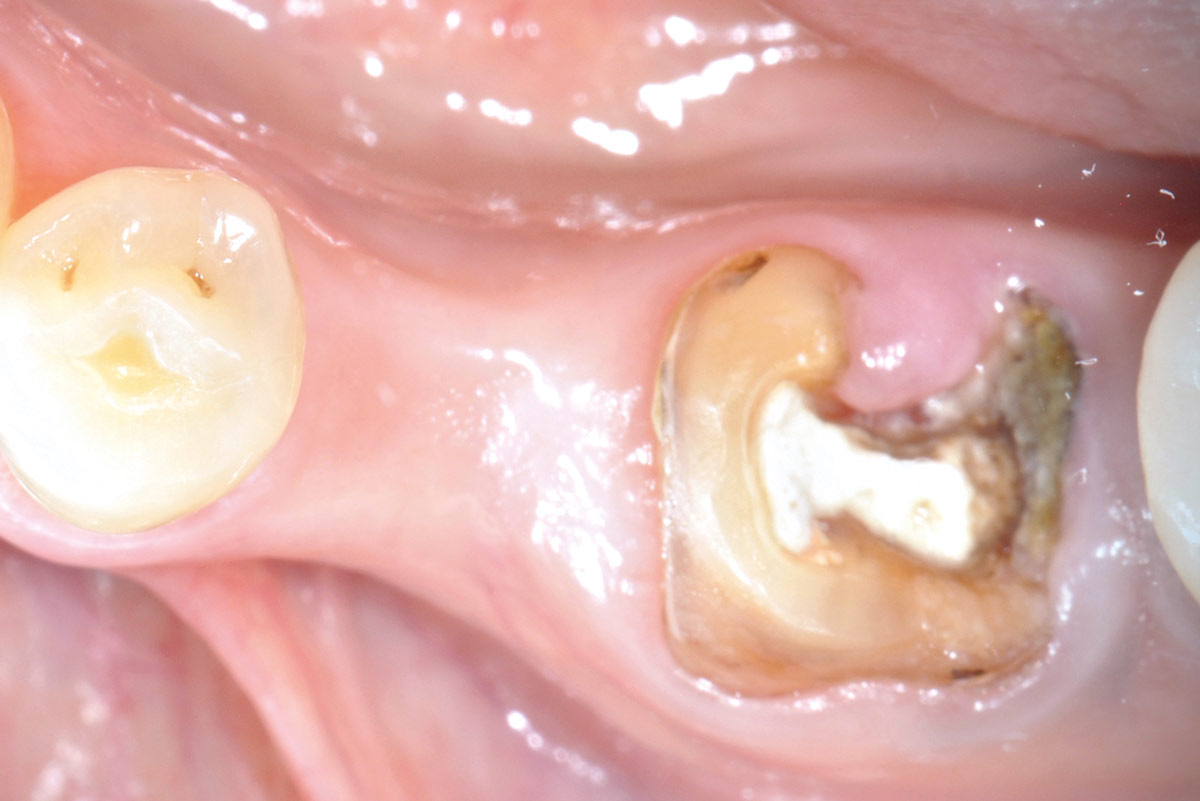

02/11 - Clinical situation before tooth extractionImmediate implantation with maxresorb® - Dr. M. Frosecchi

Clinical situation before extraction